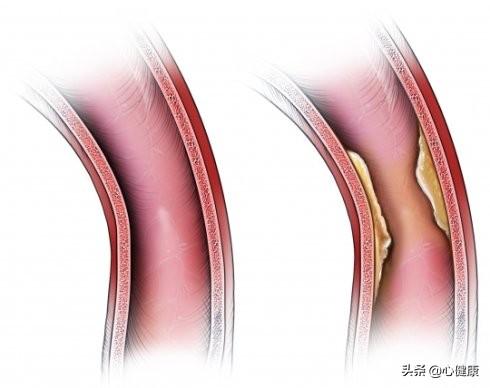

冠状動脈性心臓病は、患者の冠状動脈の血管が何らかの理由で狭窄閉塞し、血液酸素エネルギーの正常な流れに影響を与えるため、胸が締め付けられるような症状を引き起こす可能性があり、患者の日常的な行動が供給よりも多くのエネルギーを消費すると、一連の臨床症状が発生し、胸が締め付けられるような症状は典型的な症状の1つです。

先ほど、胸が締め付けられるような症状は一般的であると言いましたが、気管支炎、喘息、肺水腫、肺塞栓症、胸水、気胸、脊髄由来の疾患などが引き金になることがあります。病気のない人でも、感情的・精神的な変化によって胸が締め付けられることがある。 これは神経学的な要因の役割によるもので、患者は最近のストレスや長期の安静不足によって神経障害を患い、その結果、対応する血管が痙攣性収縮を起こし、血液と酸素の正常な供給に影響を及ぼすことがあり、血管内にプラークが形成されるのではなく、血管の全体的な変化によって引き起こされることがある。前者の場合、実際に原因となる病変がないため、長引く傾向があり、患者は自己調節の後に回復することができる。後者の場合、病変が治療されない限り、患者は回復することはなく、時間とともに状態は徐々に悪化し、生命を脅かすことになる。

冠動脈造影が正常であっても、心筋虚血が全くないとは言えない患者もいることは認めなければならない。というのも、人間の目は直径0.4-0.5mm以上の太い血管の狭窄や病変の存在しか見ることができず、前方小動脈、細動脈、毛細血管などの微小血管は冠動脈造影だけでは評価できないからである。胸が締め付けられるような症状があり、心筋虚血の証拠があるにもかかわらず、冠動脈造影が正常である人がいるのはこのためである。

1、冠動脈の急性血栓症と痙攣。冠状動脈性心臓病の大部分の病態生理的基礎は冠状動脈アテローム性動脈硬化症であるが、冠状動脈性心臓病患者の中には冠状動脈のプラークが少ししかなく、狭窄があまり強くなく、狭心症や心筋梗塞さえも冠状動脈内の急性血栓症や冠状動脈の攣縮が原因である。筆者は30代男性の急性梗塞患者に会ったことがあるが、冠動脈の結果はプラークが少ししかなく、冠動脈内の急性血栓と自己溶解が原因であることを考慮した。

2.冠微小血管疾患。冠微小血管疾患(CMVD)とは、様々な病原因子の影響下にある前部小冠動脈および小動脈の構造的および/または機能的異常によって引き起こされる労作性狭心症または心筋虚血の客観的証拠の臨床的症候群を指す。冠動脈には前部小動脈(直径0.1~0.5mm)、細動脈(直径0.1mm未満)、心外膜下冠動脈(直径0.5~5mm)の3つの部分がある。 冠動脈細動脈には前部小動脈と細動脈が含まれ、その構造的・機能的異常も狭心症やその他の臨床症状を引き起こす。

冠動脈造影検査では、大血管の問題は検出されるが、冠動脈小血管の問題や、微小循環が存在する微小循環けいれんは検出されない傾向がある。多くの場合、冠動脈造影では問題を発見する方法はない。

狭心症にはもう一つ、血流が悪くなるという特殊な条件があるからだ。狭心症の発症は通常の狭心症と違いはなく、労作、感情的興奮、寒冷などが引き金となり、狭心症発症時の後胸骨部や前胸骨部の痛みや不快感、胸の締めつけ感などがあり、安静にしていれば緩和され、狭心症発症時に心電図がST-T変化で変化し、重症例では心筋酵素まで上昇することがある。狭窄があっても、そのような明らかな臨床症状には至らず、ステント留置の適応にはならないが、狭心症はより明らかである。

この種の患者の冠動脈造影画像を注意深く見ると、この種の人の血流は比較的遅いことがわかる。 正常な人に造影剤を注入した後、冠動脈は心臓の1、2回の拍動ですぐに満たされるが、血流の遅い患者の冠動脈は心臓の3、4回の拍動、あるいは5、6回の拍動で満たされる必要がある。 冠動脈の充血が遅いため、正常な血液の排出が心筋の必要量を満たすことができず、心臓の前部に不快感が生じる。

まず第一に、画像診断では心臓の太い血管と太い枝を見て、微小循環は見ることができない。心臓の微小循環が悪いために胸が締め付けられるような症状を繰り返す人もいるが、心臓の微小循環障害は血管の内皮機能の低下に関係している可能性がある。例えば、長年の喫煙、長年の糖尿病、高血圧などが心臓の微小循環障害を引き起こす可能性がある。